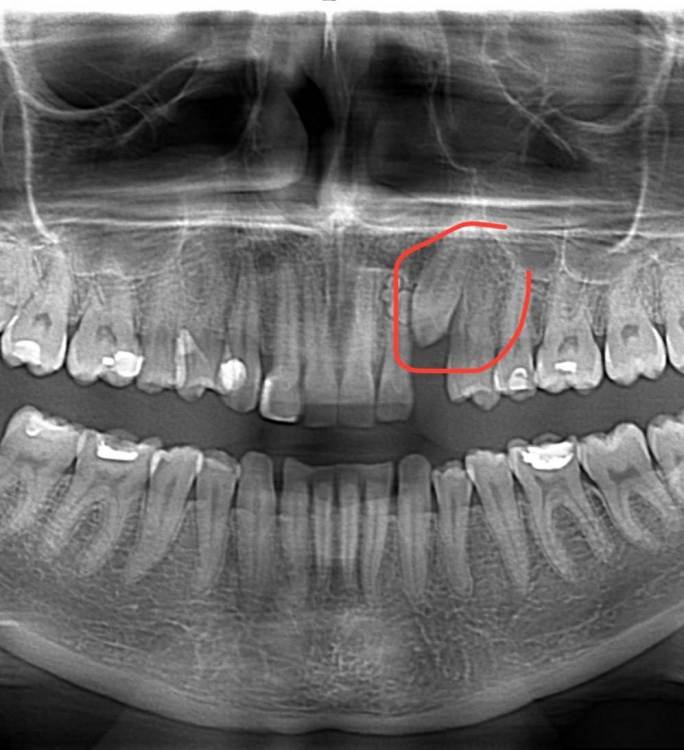

Alexandra_s Опубликовано 27 января, 2022 Поделиться Опубликовано 27 января, 2022 Добрый день! У меня в десне сидит непрорезавшийся клык (молочный удалили в 15 лет, сейчас мне 32..ходила с пластиковым протезом) и вот решилась что то с ним делать. В сентябре мне поставили брекеты, а вчера надрезали десну прицепили на зуб цепочку, десну зашили. Через 10 дней иду к орту, начнут тянуть. Хирург сказал что клык очень плотно и основательно сидит в десне и непонятно вырастет или нет. Меня это очень морально сломило, получается такие эстетические муки и напрасно. Какие могут быть прогнозы? Всегда ли они вытягиваются и за сколько? ? Клык на фото, кажется ну совсем чуть чуть. Ссылка на комментарий